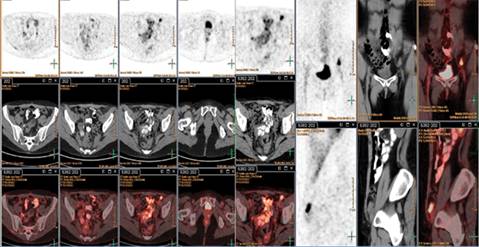

Inicia seis días previos a su ingreso con diplopía bilateral, mareo e inestabilidad postural. A su ingreso se presenta alerta con nistagmus multidireccional no fatigable, trofismo y fuerza muscular normal, destaca arreflexia y marcha atáxica con signo de Romberg presente. Se realiza resonancia magnética que se reporta normal con subsecuente punción lumbar, no se reportan hallazgos relevantes en citología y citoquímica, la paciente presenta anticuerpos anti-Yo positivos (≥ 1:10), por lo que se establece síndrome paraneoplásico con recurrencia de la enfermedad confirmada por tomografía por emisión de positrones a nivel ganglionar inguinal izquierdo (Figuras 1 y 2).

Figura 1: Tomografía por emisión de positrones con actividad metabólica a nivel ganglionar inguinal izquierdo en relación a depósito secundario de tumor primario ya conocido.

Figura 2: Tomografía por emisión de positrones con adenopatía inguinal izquierda de 16.6 mm asociado a metabolismo.